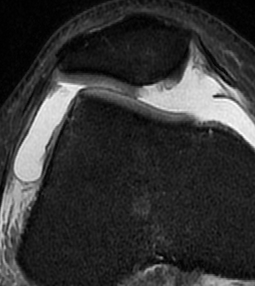

MRI

Demonstrates

- MPFL tear

- cartilage damage

- loose body